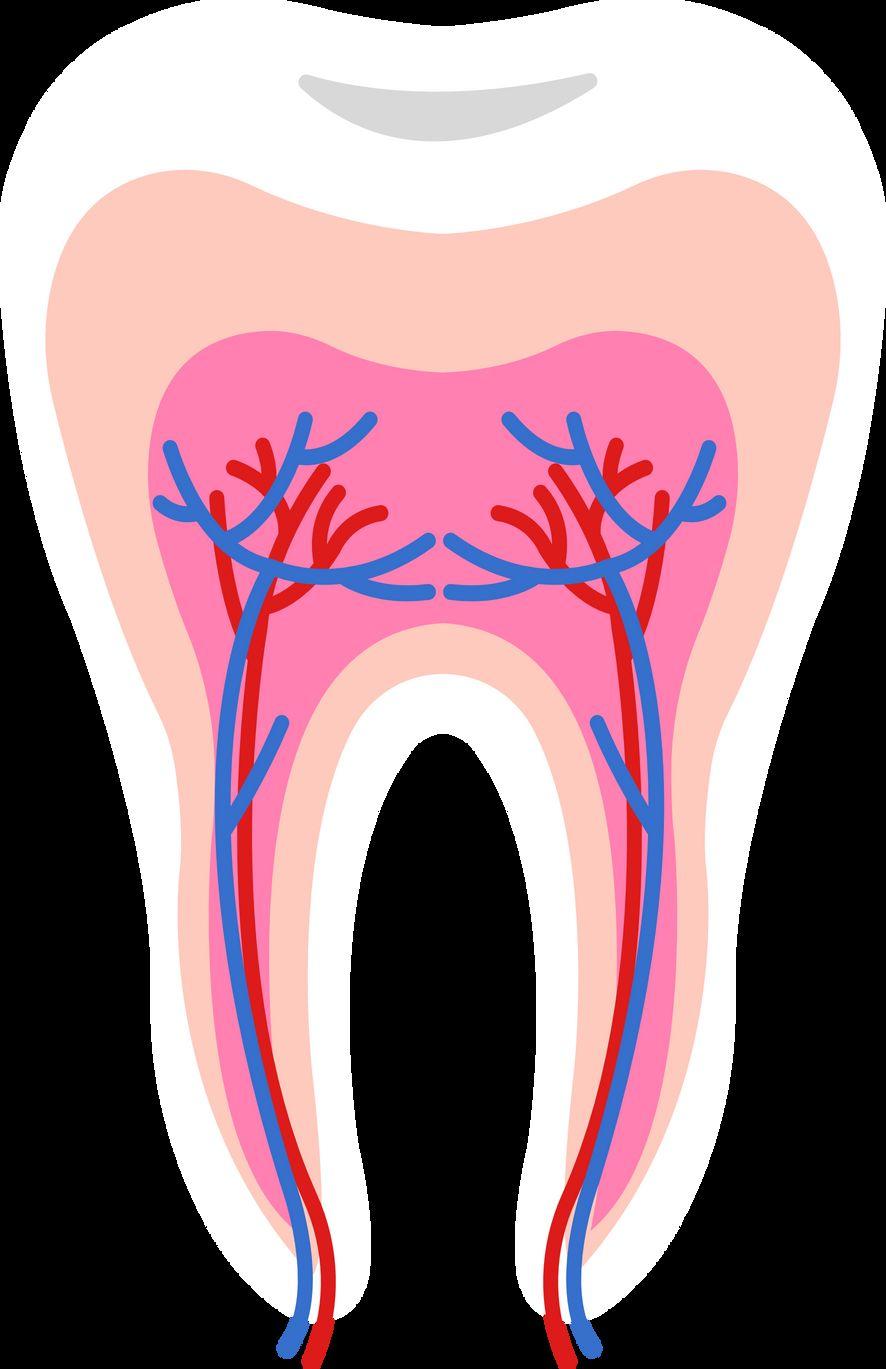

Tooth anatomy & cavities

Bacteria produce acidic byproducts

Acid removes minerals from teeth